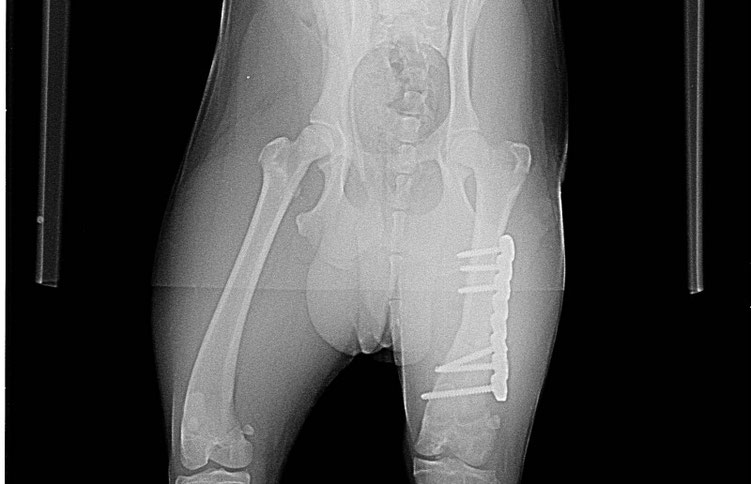

Bei den erneuten Röntgenaufnahmen hat sich jedoch auch gezeigt, wie schön der Bruch des hinteren Oberschenkels verheilt ist - um so wichtiger ist es für Kirby und sein zukünftiges Leben, dass nun alles daran gesetzt wird, auch sein Vorderbein zu richten.